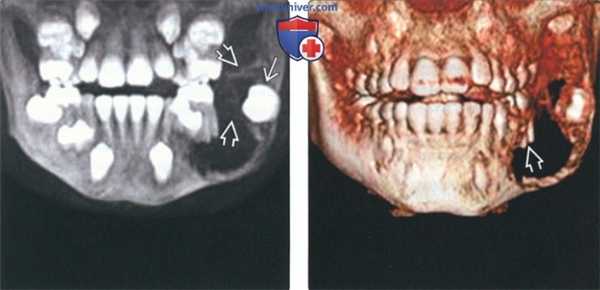

(Слева) На трехмерной реконструкции визуализируется им-пактный второй моляр, смещенный амелобластической фиброодонтомой (АФО). Обратите внимание на мелкие включения с плотностью зуба в опухоли.

(Справа) На аксиальной КЛКТ у этого же пациента визуализируется АФО, содержащая множественные мелкие кальцинаты с плотностью зуба. Данный срез выполнен ниже импактного зуба. Обратите внимание, что кальцинаты не похожи на зубы.